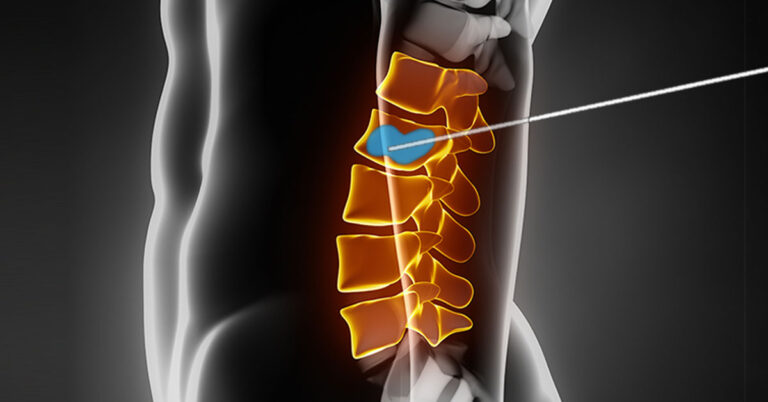

ترک سیگار قبل از انجام جراحی فیوژن ستون فقرات یکی از موارد قبل از عمل است که توسط جراح معالج از شما درخواست خواهد شد. اما اگر این پرسش ذهن شما را به خود مشغول کرده است که چرا ترک سیگار قبل از انجام جراحی فیوژن ستون فقرات لازم...